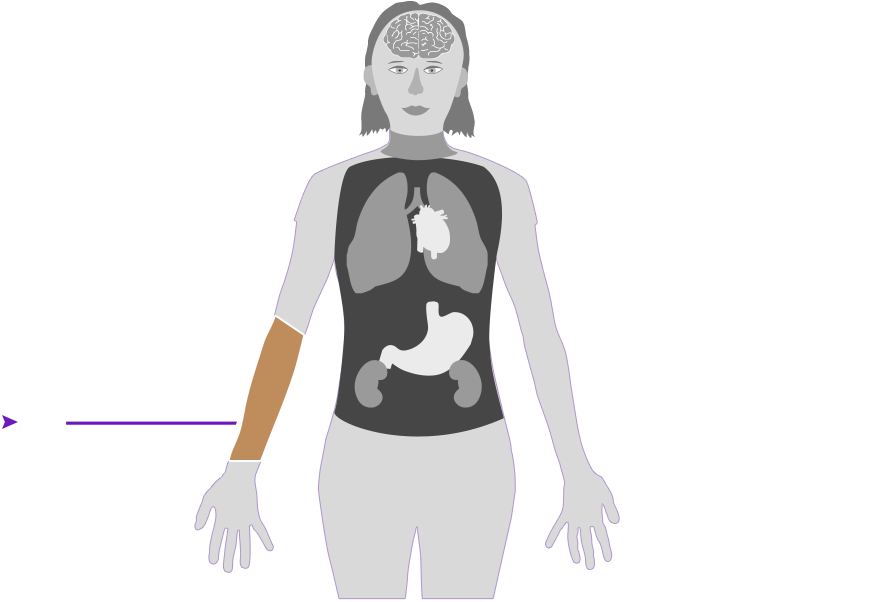

Check out how mercury can affect the human body. Click on the different parts of the body to see what can happen when people are poisoned by mercury. How serious these health effects are may vary depending on how much mercury gets into your body — and how long you breathe it in.

Health effect caused by breathing in high levels of mercury vapors (fumes) over a short period of time

Health effect caused by breathing in high levels of mercury vapors (fumes) over a short period of time  Health effect caused by breathing in lower levels of mercury vapors over a long period of time

Health effect caused by breathing in lower levels of mercury vapors over a long period of time